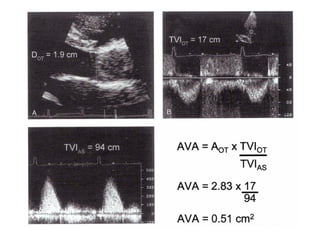

Gorlin formula (Continuity equation)

• Based on Newton's second law of thermodynamics, involving

conservation of mass

• The volumetric flow rate through the CVS is constant, assuming that

the blood is noncompressible and the conduct is inelastic

• So flow across a stenotic or regurgitant orifice is same as a proximal

flow across a known area and velocity

• A1 x TVI1 = A2 x TVI2

• Used to find AVA even in the presence of AR or LVD

Gorlin formula (Continuityequation) • Based on Newton's second law of thermodynamics, involving conservation of mass • The volumetric flow rate through the CVS is constant, assuming that the blood is noncompressible and the conduct is inelastic • So flow across a stenotic or regurgitant orifice is same as a proximal flow across a known area and velocity • A1 x TVI1 = A2 x TVI2 • Used to find AVA even in the presence of AR or LVD